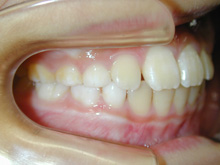

患者様は上下顎歯列弓の狭窄と上下顎前歯の叢生を主訴としてお母様とともに来院されました。

近隣のかかりつけの歯科医院で小児の頃より将来的な矯正治療の必要性をお話しいただいたそうです。

そのころからの将来矯正歯科治療の場合には抜歯の必要がある可能性も指摘されたともお話があったそうです。

犬歯関係・臼歯関係は良好です。

犬歯関係・臼歯関係は良好ですので、かみ合わせを崩さないように矯正治療をすすめます。

上下顎前歯の叢生を改善するために上下顎両側第1小臼歯を4歯抜歯して治療します。

0.14インチラウンドのニッケルチタンワイヤーで治療開始して0.16×0.16レクタンワイヤーで治療をすすめていき叢生を改善します。

できたスペースを利用して叢生の改善と臼歯のかみ合わせの改善を行います。

治療の前に叢生のためずれていた中切歯の正中は一致しています。犬歯関係、臼歯関係も1対2歯でよく咬んでいます。

口腔衛生状態が治療中に不良でした。

装置がとれ、歯列が改善されたので口腔衛生状態の改善を期待してブラッシング等のオーラルセルフケアに重要性を説明しました。

後戻りを防ぐには保定が重要でリテーナーの使用を強く指導しました。